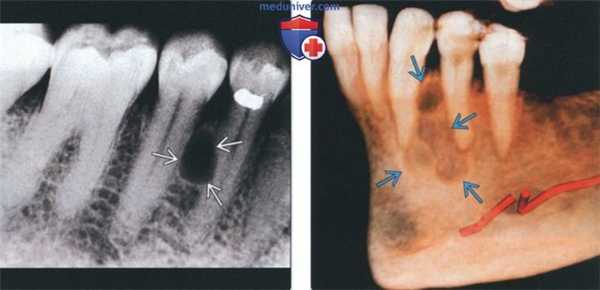

(Слева) На периапикальной рентгенограмме нижней челюсти справа между первым и вторым премоляром (наиболее типичная локализация) определяется боковая периодонтальная киста. Обратите внимание, что киста имеет классический вид слезы.

(Справа) На сагиттальной трехмерной реконструкции (КЛКТ) между первым премоляром и клыком нижней челюсти определяется многокамерное объемное образование. Была выполнена биопсия, подтвердилась гроздевидная одонтогенная киста (ГОК).